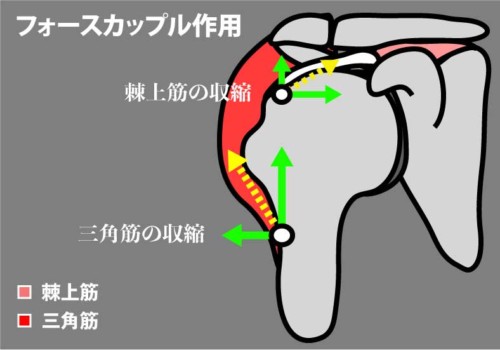

① 肩峰下インピンジメント(腱板損傷)

機序

フォースカップル破綻:棘上筋(求心化)<三角筋(上方剪断)になると骨頭が上方偏位→肩峰下で棘上筋腱や滑液包が衝突。